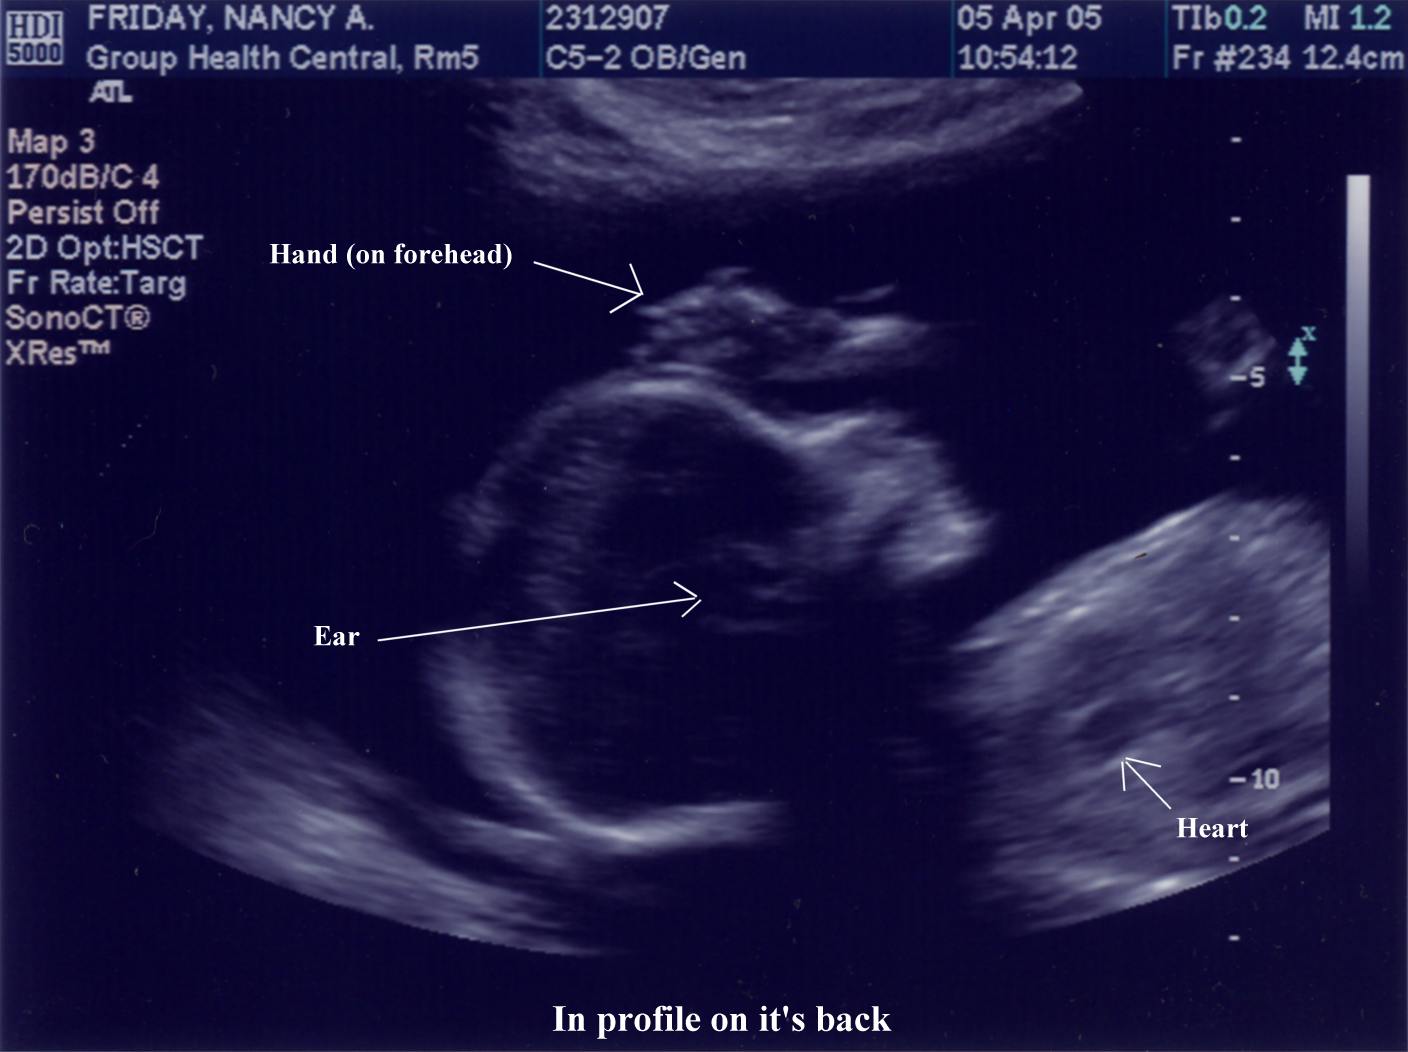

April 5, 2005 - 20.5 weeks (18.5 weeks from conception)  |